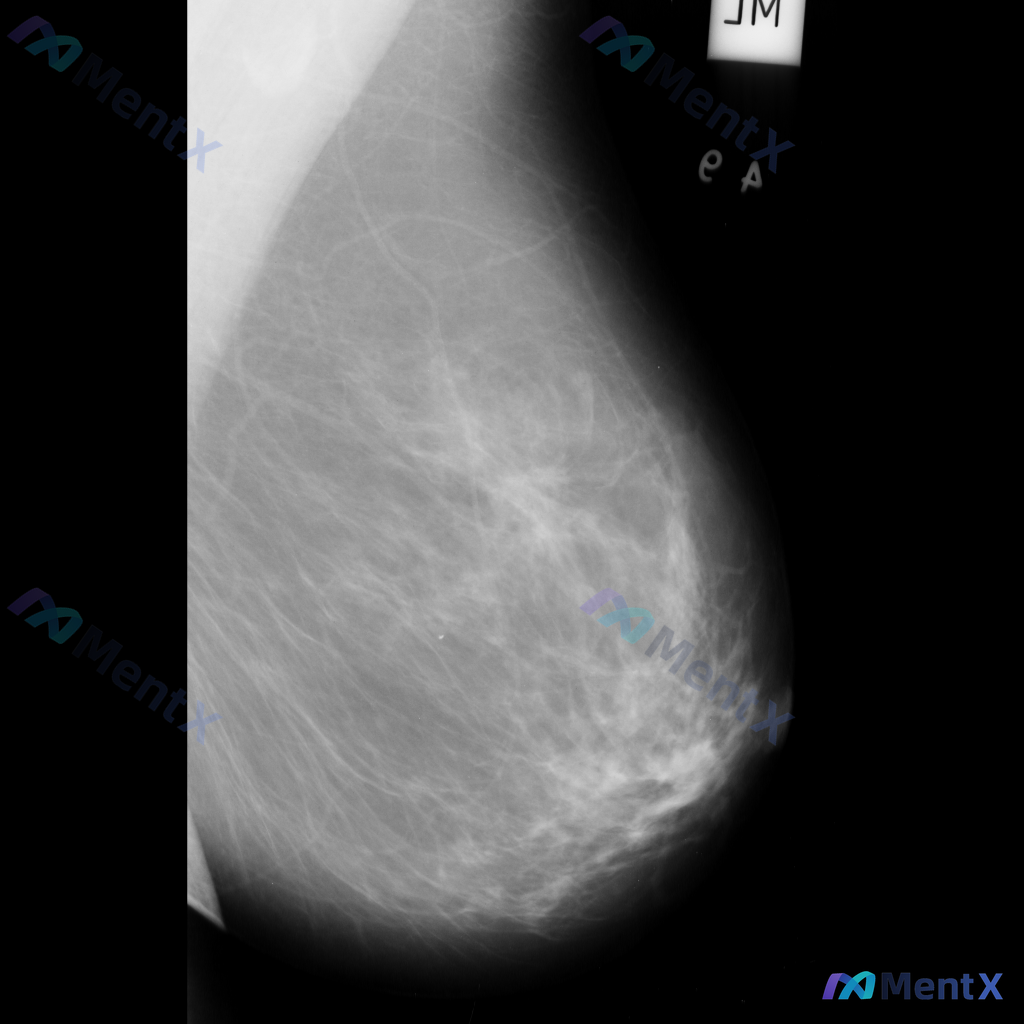

整理到一张乳腺钼靶影像资料,大家一起讨论下。 影像表现大概是这样: - 异常区域位于乳腺下象限偏外侧 - 可见一局限性致密影,形态大致呈卵圆形或不规则形 - 边缘部分清晰,局部可能模糊或有细微毛刺样改变 - 致密影密度高于周围脂肪组织,与纤维腺体组织密度相似或略高 - 周围乳腺小梁结构似有轻微的牵拉...

刚看到这个病例,特点很典型,整理一下病例信息和分析思路分享给大家。 病例基本信息 - 患者:32岁女性,未孕 - 主诉:发现单侧乳房自发性无痛血性溢液,浸湿衬衫内侧 - 既往史/家族史:无恶性肿瘤家族史,月经自13岁来潮后一直规律,无发热咳嗽,生命体征正常 - 查体:未触及乳房肿块,无红斑、无硬结...